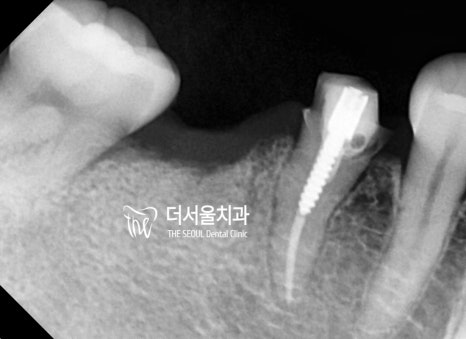

초진 파노라마

일단 이분은 치아가 많이 썩어서

살릴 수 없는 곳들은 발치를 진행하였습니다.

이곳들은 추후 임플란트 식립을 통해

빈 곳을 메꿔주기로 했죠.

다행히 살릴 수 있는 곳들도 있었는데요.

그러나 이곳도 꽤 많은 부분이

감염이 되어 있는 상황이었습니다.

이곳들은 신경치료 및 포스트를 진행하여

살릴 수 있을 때까지 자연치를 살려보기로 했습니다.

우선 잔존조직이 남아있지 않도록

깨끗하게 발치를 하였으며,

살릴 수 있는 곳들은 근관치료를 했습니다.